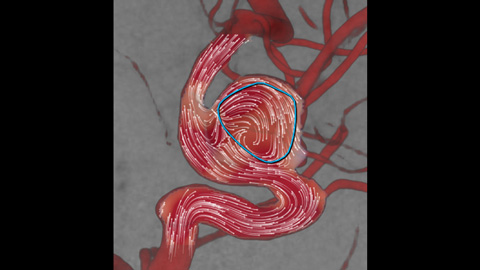

AneurysmFlow

Die funktionelle Beurteilung des Blutflusses nach abgeschlossener Intervention kann sich als schwierig erweisen. AneurysmFlow liefert Ihnen vor und nach dem Einsetzen eines Flow Diverters relevante Informationen. Durch Darstellung und Quantifizierung von Flussveränderungen sorgt es für größere Sicherheit im Hinblick auf den Eingriffserfolg.

Durch Visualisierung und Quantifizierung von Blutflussmustern im Ursprungsgefäß und Aneurysmasack werden wichtige Informationen gewonnen, die beim Einsetzen von Flow Divertern und anderen Embolisationsgeräten Unterstützung bieten können.

Sie können Veränderungen am Blutfluss im Aneurysma vor und nach der Behandlung durch Vergleich des Mittleren Aneurysma-Flussamplitudenverhältnisses (Mean Aneurysm Flow Amplitude Ratio, MAFA) vor und nach Einsetzen des Flow Diverters beurteilen.